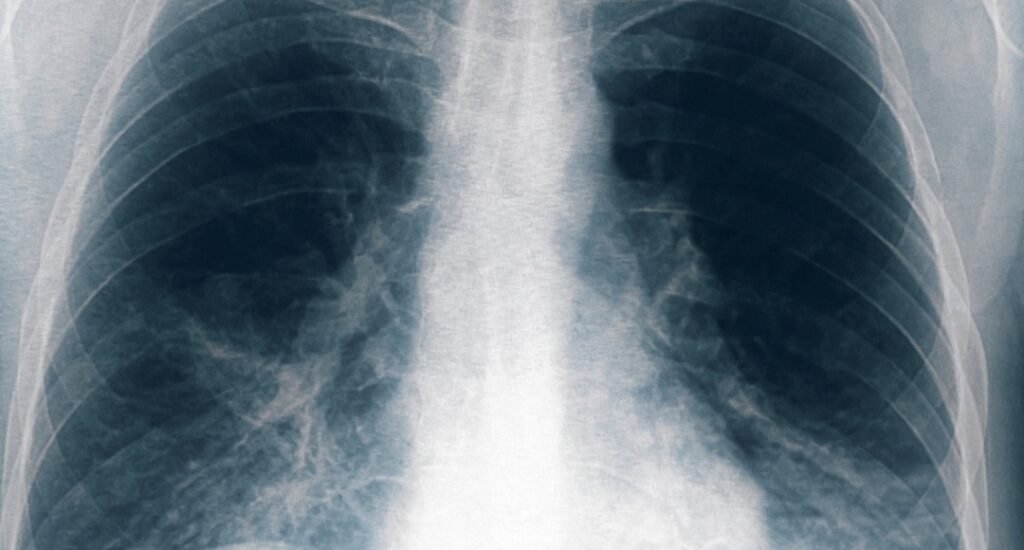

Un paciente “vinculado al conglomerado de casos de neumonía” bilateral registrados en Tucumán murió este domingo, por lo que suman cinco las víctimas fatales por esta causa, informó el Ministerio de Salud Pública provincial.

Hasta el momento se identificaron once personas afectadas por neumonía bilateral causada por Legionella, en la clínica privada Luz Médica, de las cuales cinco fallecieron.

Los primeros seis casos registrados correspondieron a cinco trabajadores de la salud y a una paciente que estaba internada en el servicio de terapia intensiva de un sanatorio privado de la ciudad de San Miguel de Tucumán, quienes iniciaron síntomas entre el 18 y el 22 de agosto, presentando fiebre, mialgia, dolor abdominal y disnea.